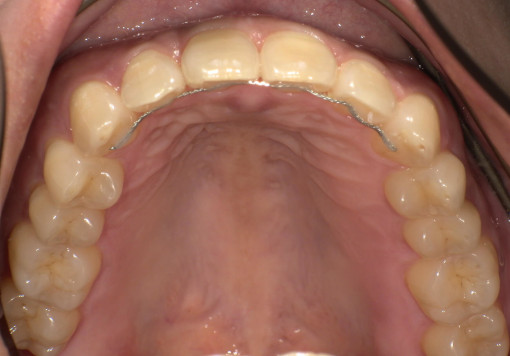

Case 04

before

after

- 主訴:前歯のガタつき・上下の歯並びの不均一を改善したい。

根管治療途中の歯を治したい - 治療内容:マウスピース型矯正装置(SureSmile)による全顎矯正。

下顎1本インプラント埋入 - 治療期間:約36ヶ月

- 診断結果:

・上下顎に叢生を認め、特に上顎前歯部の位置不良が強い状態。

・噛み合わせのズレがあり、審美性・機能性の改善が必要と判断。

・抜歯を伴わないマウスピース矯正での改善が可能と診断。

歯根破折 - 治療後経過:

・前歯部の配列が整い、正中・噛み合わせが改善。経過も良好。 - 治療費用:マウスピース矯正(SureSmile):88万円税込

インプラント45万円税込

※症例により費用は前後します。